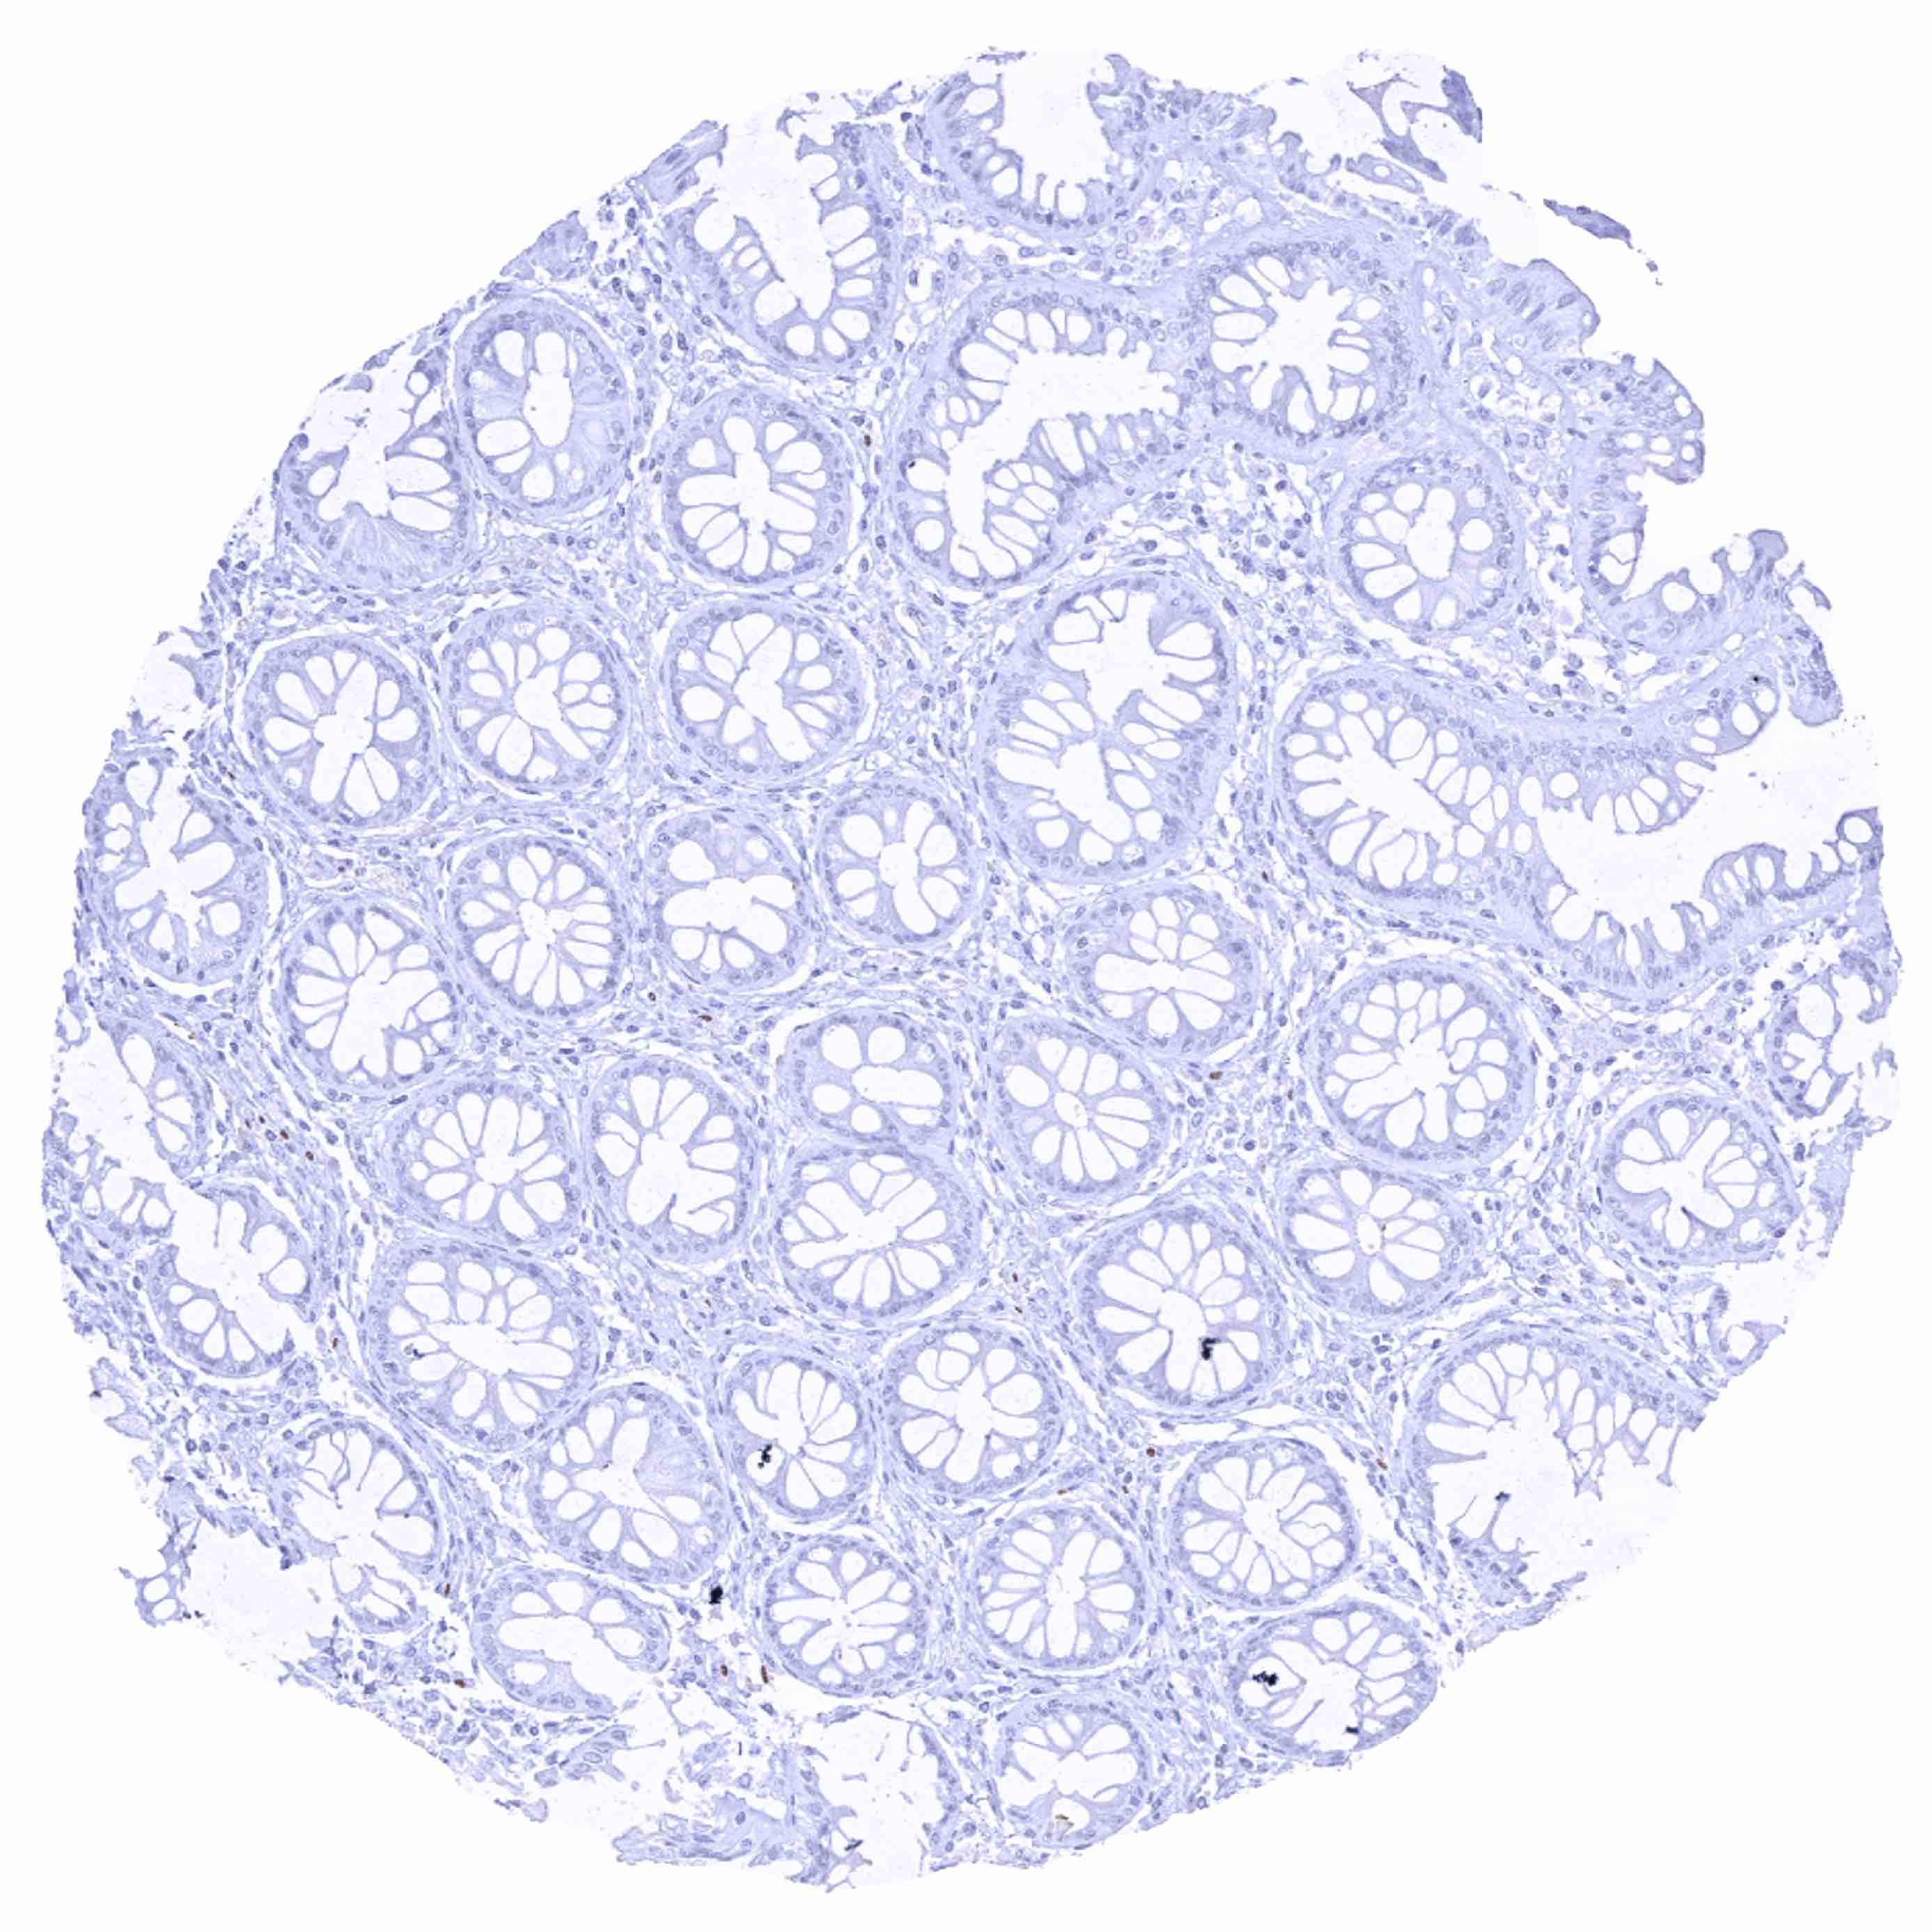

Colon descendens, mucosa